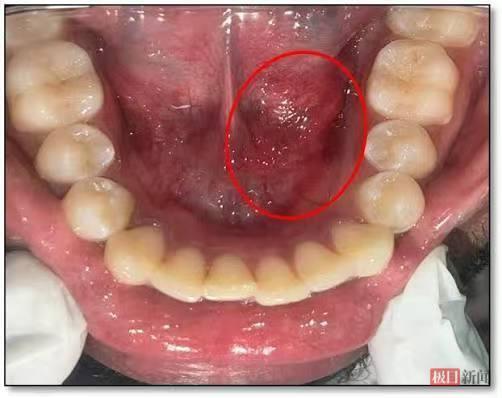

图片颌下腺导管口周围黏膜红肿

经过详细检查,口腔医学中心魏明波医生发现杨婆婆左侧颌下腺导管口红肿,按压时唾液分泌明显减少,颌下腺彩超显示腺体增大。结合临床表现,确诊其为因导管狭窄引起的“慢性阻塞性颌下腺炎”。